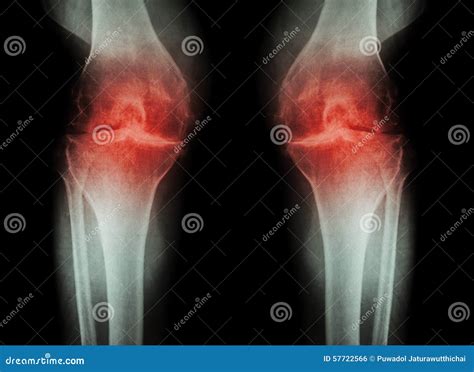

Diagnosing artritis en la rodilla involves a combination of medical history, physical examination, and diagnostic tests. The diagnostic process typically includes:

• Imaging Tests: X-rays, MRI, or CT scans may be used to visualize the knee joint and assess the extent of damage.

• Swelling: Inflammation and swelling around the knee joint.